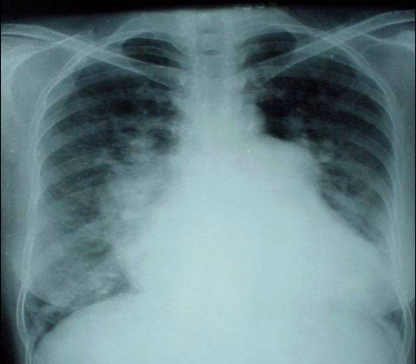

3.    先天性心脏病怎么诊断?

可通过心脏听诊、胸部X线片、心电图、心脏彩超等检查,可以明确病变类型、程度、肺动脉高压为进一步的治疗方案的选择提供依据。

图片 3.png